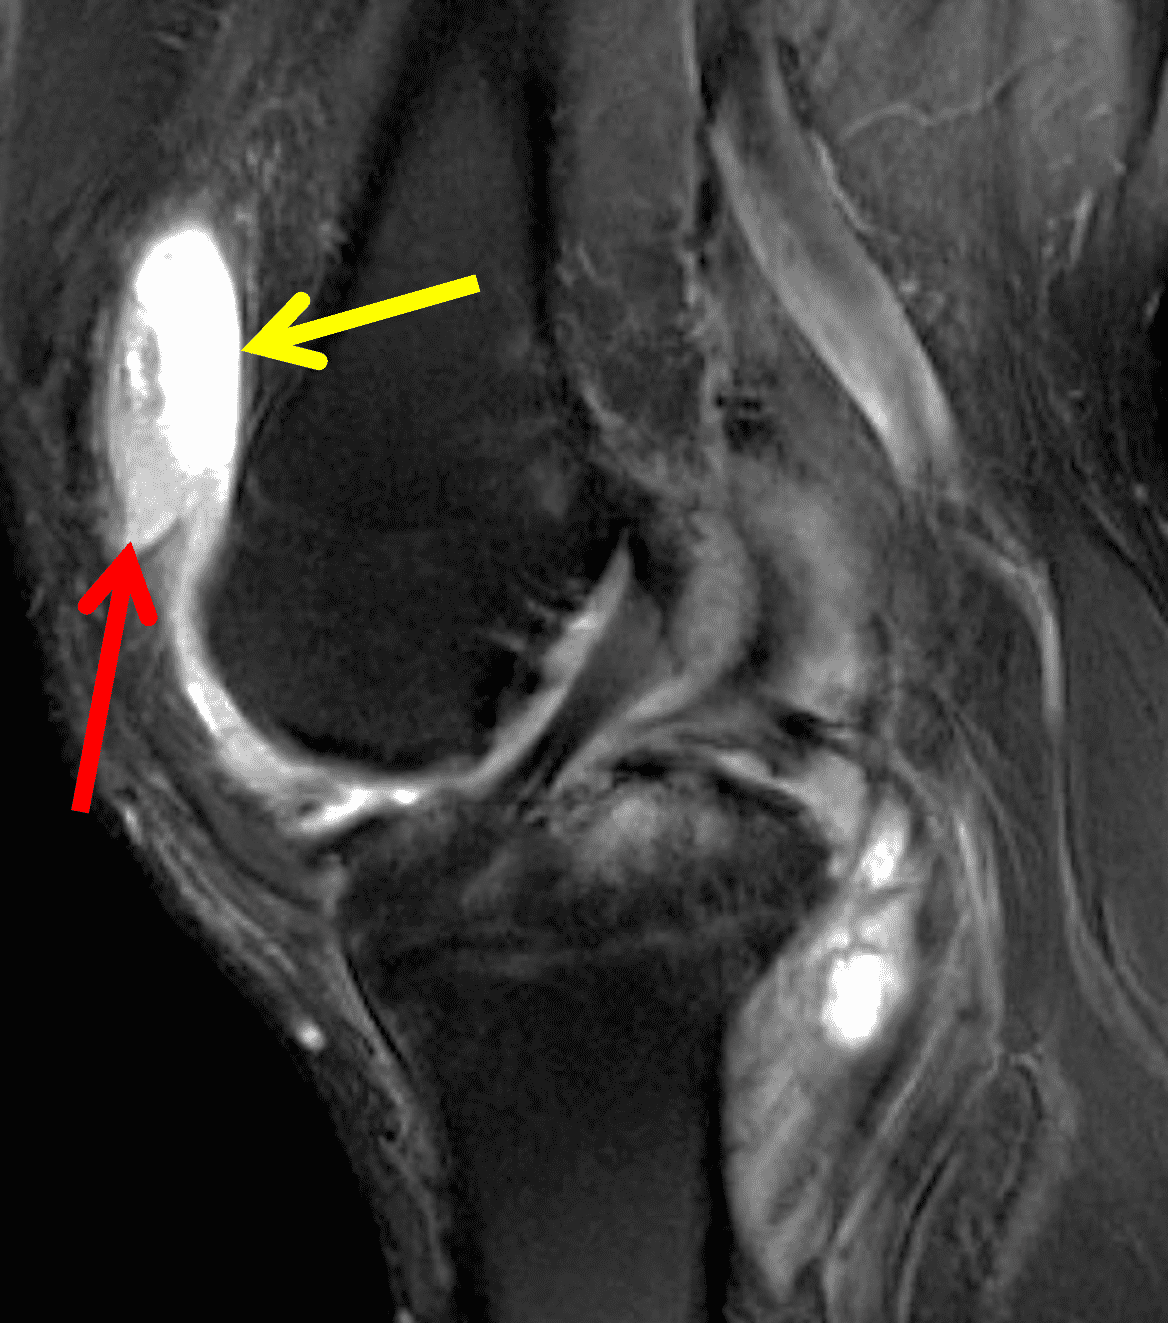

Figure 6: Rheumatoid arthritis. (6A) Sagittal fat-suppressed T2-weighted image demonstrates an effusion (yellow arrow) and synovitis (red arrow) in the suprapatellar recess. (6B) Coronal fat-suppressed T2-weighted image shows extensive, relatively uniform cartilage loss in the medial and lateral compartments and subchondral osteitis (asterisk) in the medial tibial plateau. (6C) Axial fat-suppressed T1-weighted image obtained following intravenous contrast administration shows the enhancing synovitis (red arrow) and the non-enhancing joint effusion (yellow arrow). Note the uniform cartilage loss of the patella. This patient had polyarticular disease.